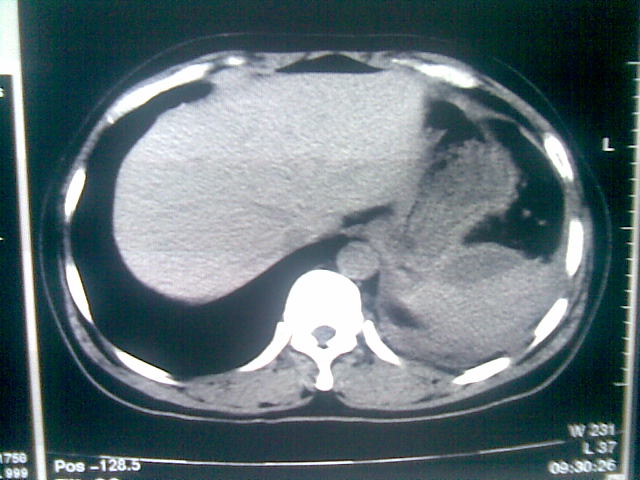

标题: CT23981:男,38岁阑尾炎术后透视胸腔积夜!做CT如下!积液包 [打印本页]

标题: CT23981:男,38岁阑尾炎术后透视胸腔积夜!做CT如下!积液包

可能与阑尾术后关系不太大,1.胸膜增厚粘连见少量气体。包裹脓气胸?左侧网膜囊脓肿?

.胸膜增厚粘连见少量气体。包裹脓气胸

左侧胸膜增厚、粘连+包裹液气胸。